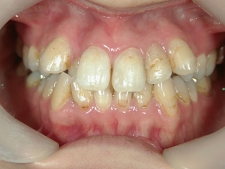

矯正歯科 治療後矯正歯科 全顎ワイヤー矯正 治療後矯正歯科(全顎ワイヤー矯正)治療後

no.7_6967_治療後_右_01_640_480_やや高画質.jpgno.7_6967_治療後_正面_01.jpgno.7_6967_治療後_左_01.jpg